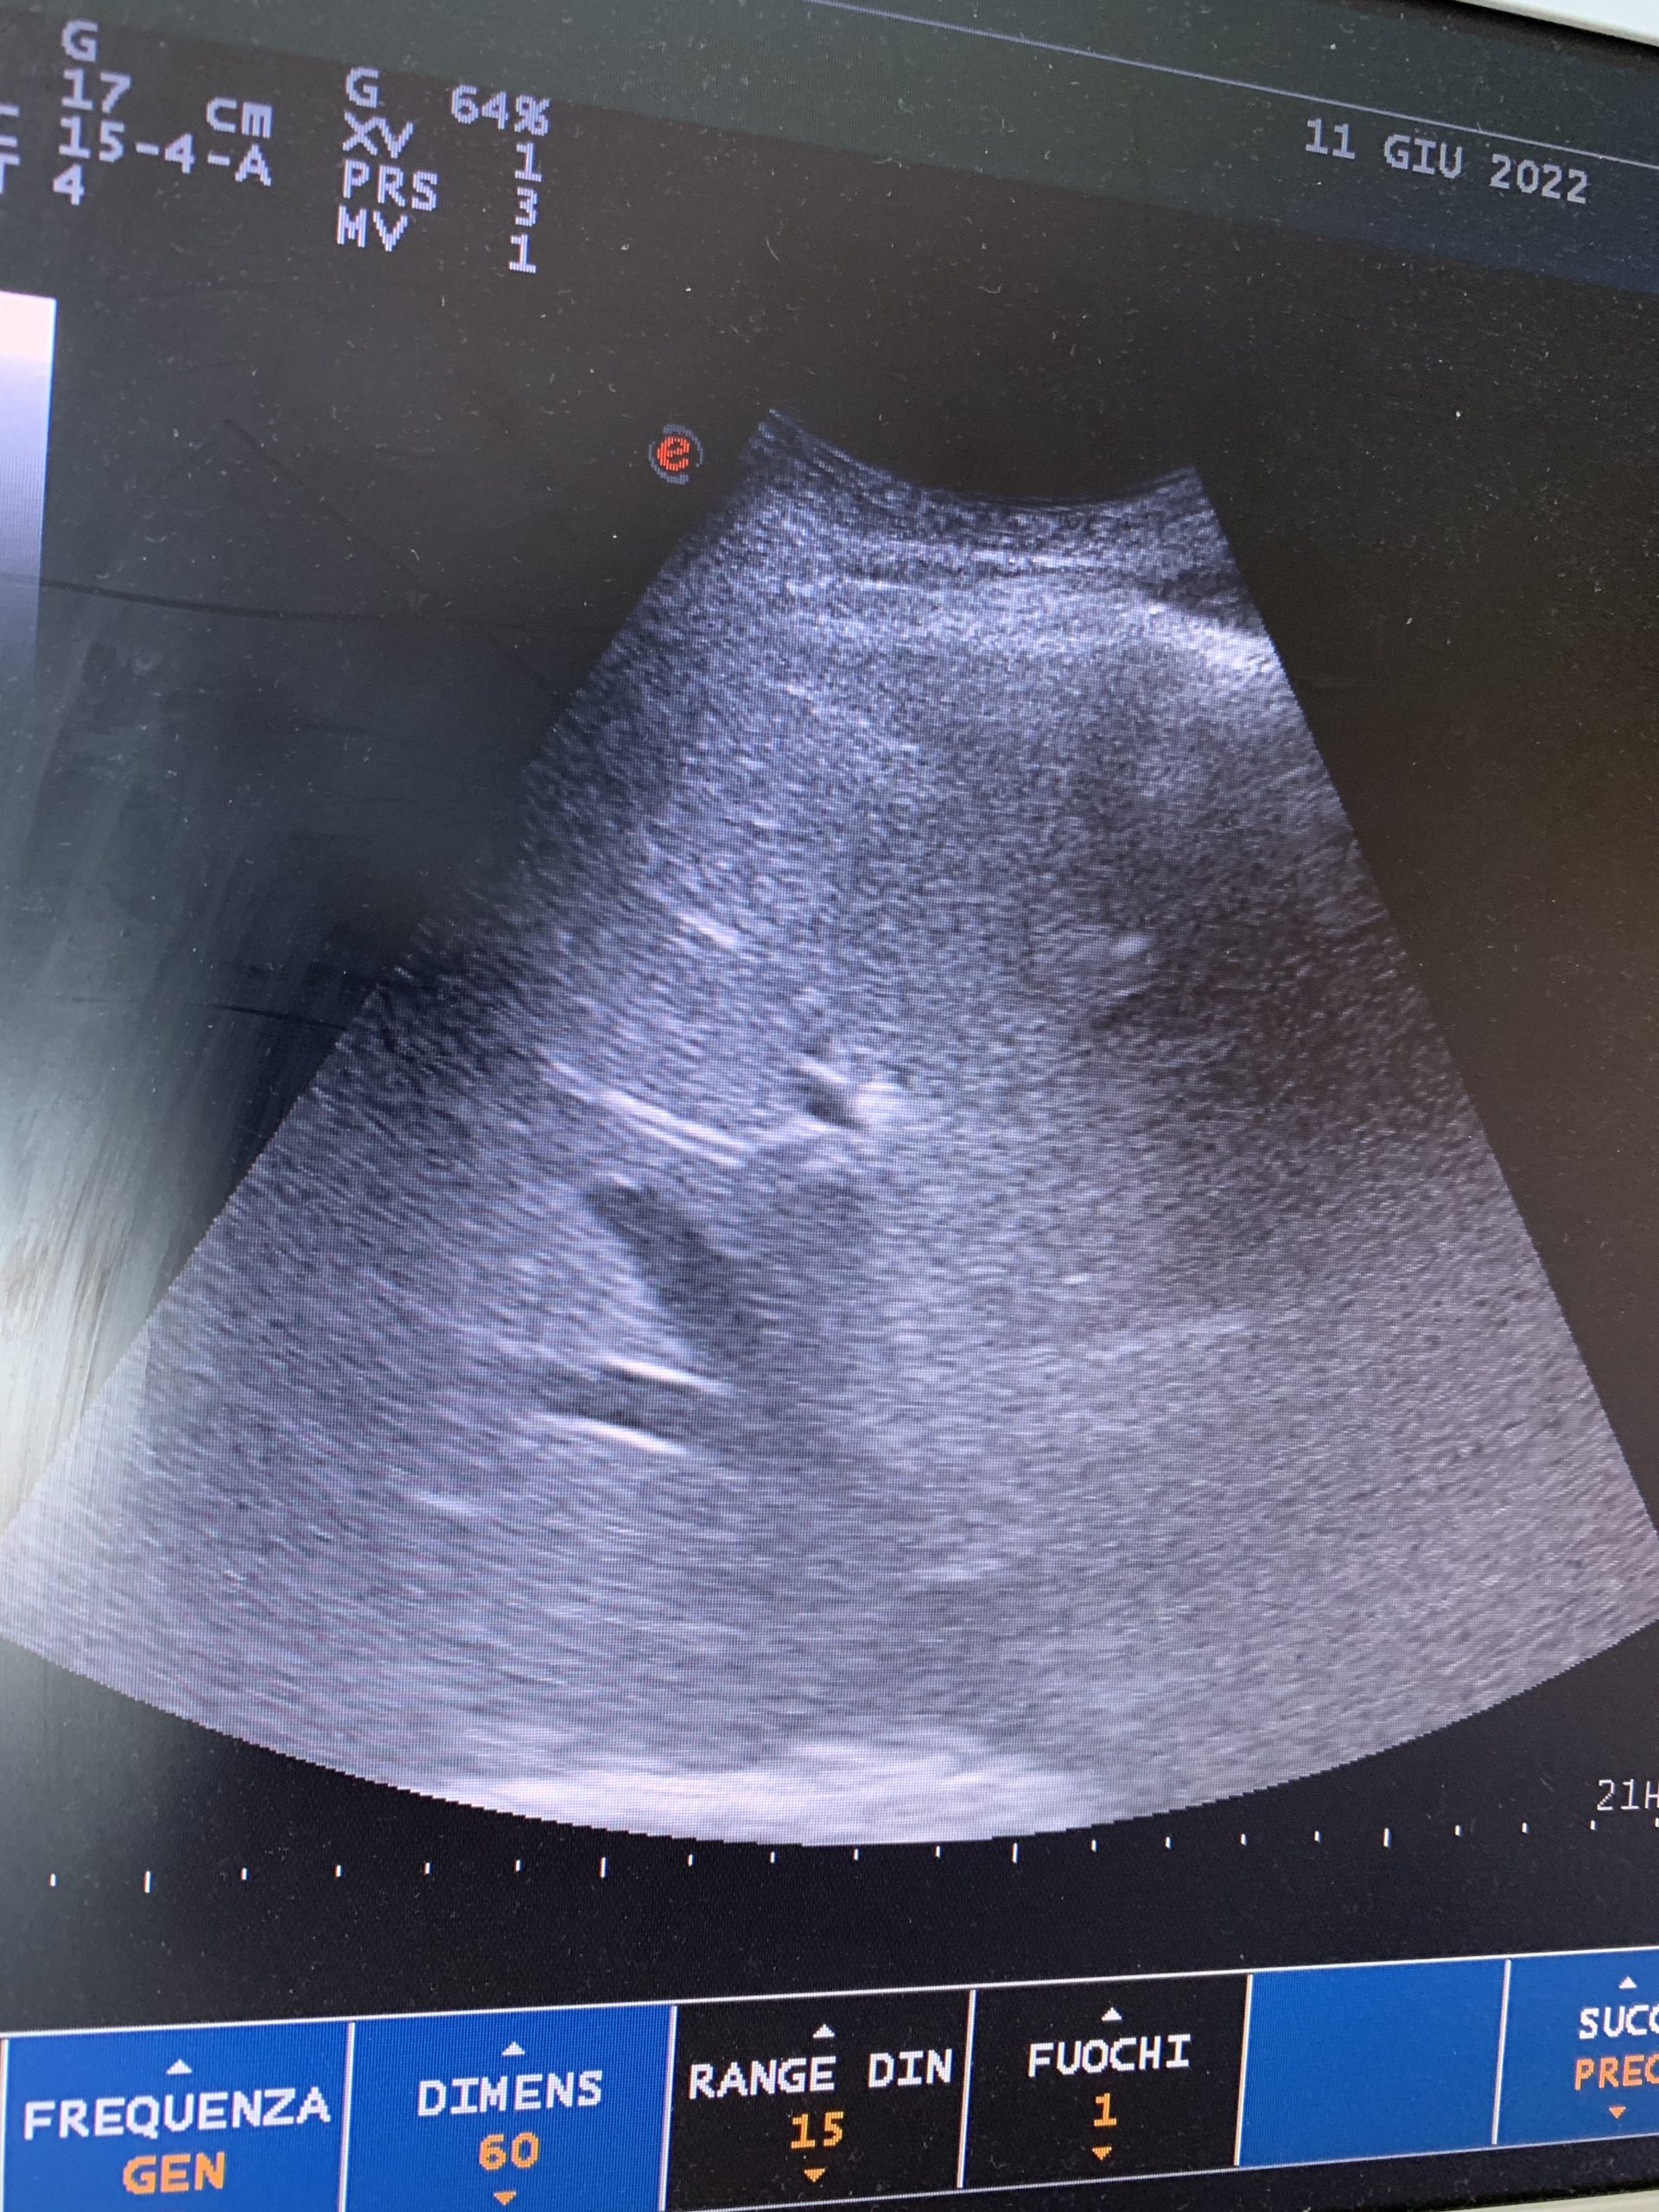

Il mio fegato, il diaframma ed i polmoni.

Ecografia a letto per controllare la respirazione cardiaca accettarata da stamattina.

È tutto nella norma.